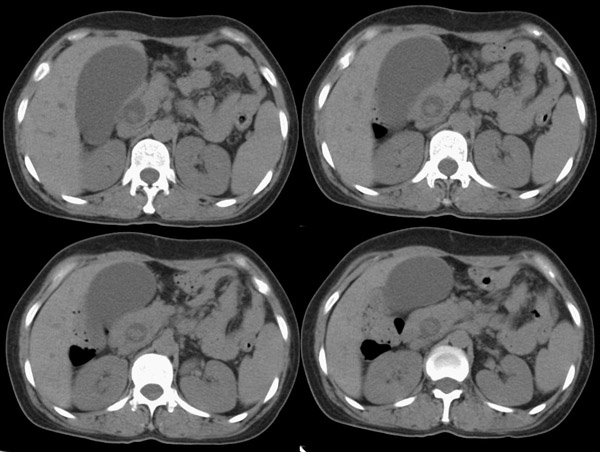

局部1mm薄层重建:

整个胆道系统内可见多发蛔虫钙化改变,胆道扩张.

胆总管结石并肝内外胆管扩张、肝左叶肝内胆管结石、胆囊大。

胆总管结石(蛔虫钙化)并低位胆系梗阻